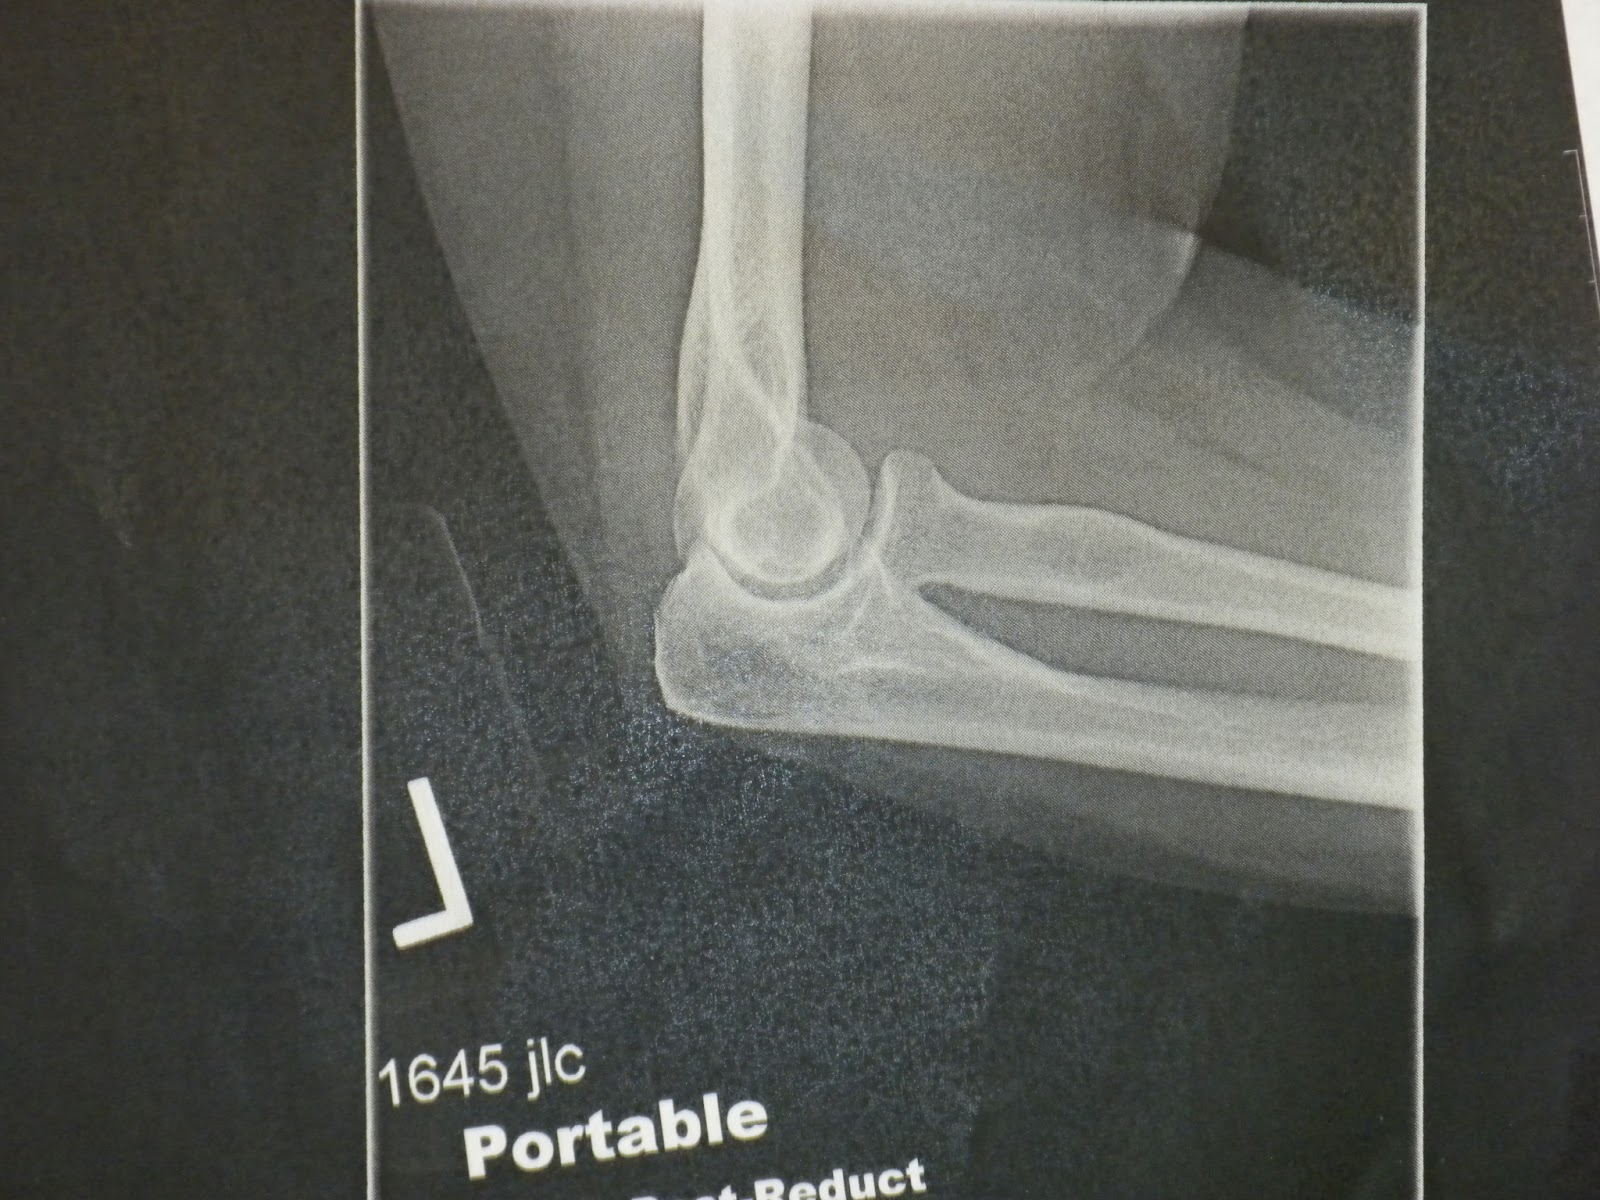

Because I am a memoirist, I am compelled to share the x-ray of my dislocated elbow:

The lower bone is supposed to be tucked in next to the upper bone. I know the bones have names, but I can barely stand to look at this, let alone be accurate at the same time. Melissa, of course, thought the x-ray was totally cool. The less I know about the inside of my body, the happier I am.